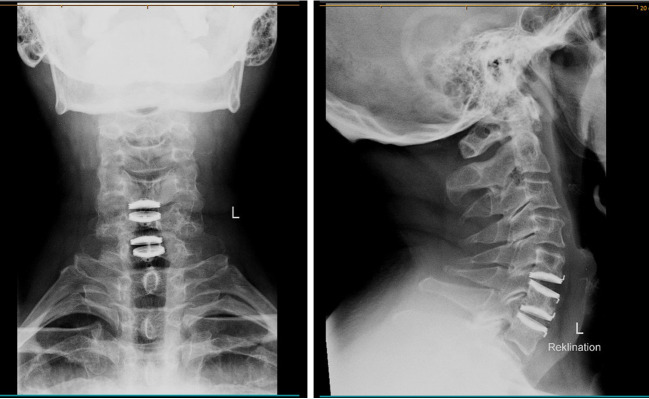

Background: The objective of this report is to present a case of two cervical spine artificial discs (Bryan Cervical Disk) that completely disappeared within 6 months as a result of a high-energy trauma more than 10 years after the initial surgery. Implant dislocation is a known complication in artificial cervical disc replacement. However, this report presents the case of an exceptional migration path with esophageal ingrowth and rectal excretion, not only for one artificial disc but for two at different times It highlights the need for long-term follow-up examinations after artificial cervical disc arthroplasty (ACDA).

Case description: The patient was seen in a Swiss outpatient spine center. He presented with a history of chronic laryngitis, which led to multiple ear, nose, and throat (ENT) diagnostic examinations without any cause being found. Migration of two cervical artificial discs was discovered incidentally in a cervical spine magnet resonance imaging (MRI), which was performed due to chronic myofascial pain in the lower extremities. The MRI showed anterior/retropharyngeal migration of one cervical disc. The second one could not be seen on the whole spine MRI. The complete patient history and radiographic findings were collected and reviewed. In addition, a whole-body computer tomography (CT) scan was done, and the patient was sent to an ENT center to rule out esophagus perforation and to verify the location of the two BRYAN © Cervical Disc.